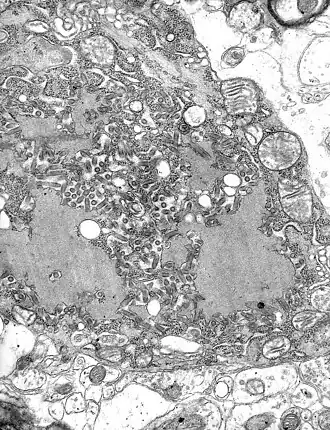

Microscopia do vírus da raiva | |||||||||||

O virião tem em geral a forma de um projétil (arredondada numa extremidade e reta na outra), podendo também ter formato de bacilo (as duas pontas arredondadas), medindo cerca de 170 nm de comprimento por 70 nm de largura.[3]

O revestimento lipídico (4, na imagem) é cercado por uma camada de espículos de glicoproteína, com cerca de 5 a 10 nm de comprimento[1] (2, na imagem). O nucleocapsídeo tem formato helicoidal simétrico (3) e é envolvido por uma camada lipídica (5).[1]